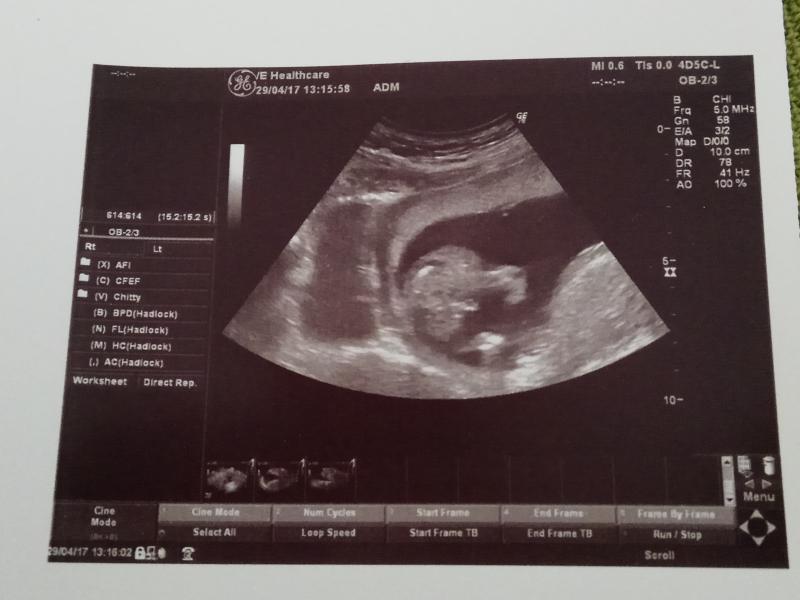

🌼 УЗИ - как включили - сразу показал мне свой писюн, мы с врачом начали смеяться и он спрятал всё 🙈 стесняшка))) сделали фоточку для папы)))